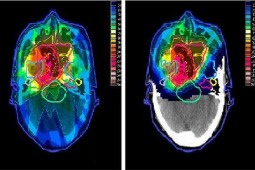

Za 250 mln zł ma powstać w Poznaniu nowoczesny ośrodek terapii protonowej. Tyle tylko, że nie wiadomo, czy będą pieniądze na jego utrzymanie, bo budżet – jak na razie - takiego leczenia nie finansuje.